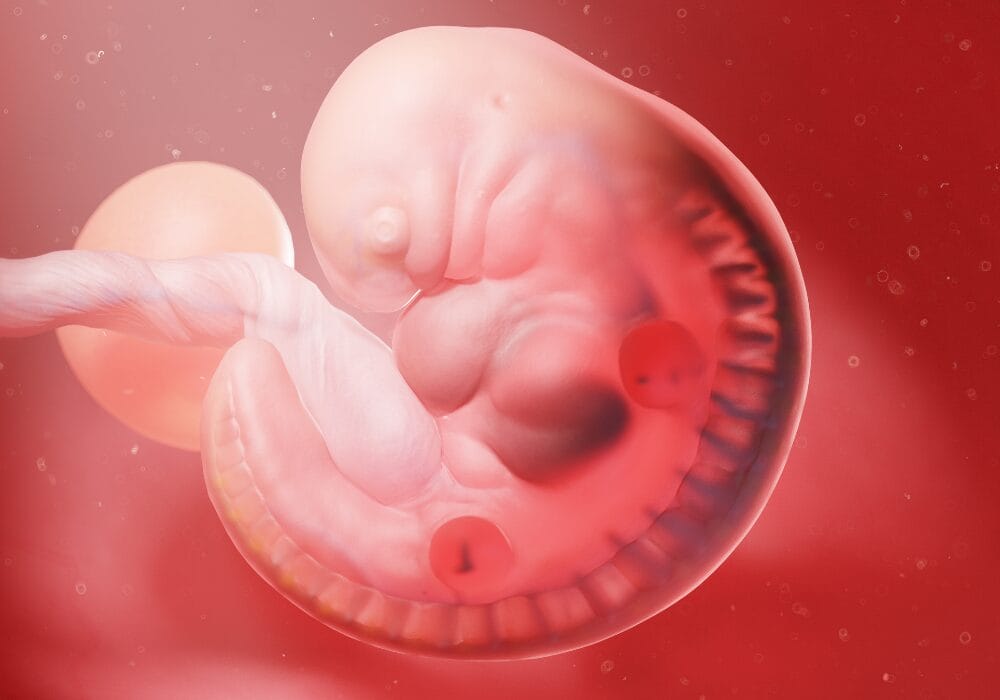

في الأسبوع السادس من الحمل يبدأ الجنين في النمو ويكبر حجمه ثلاث أضعاف كما يبدأ في التشكيل، ويكون نصف رأسه مثل الكرة، وخلال هذا الأسبوع أيضاً ينمو المخ، والكلي والكبد، والرئتان، ويبدأ بتنفس الأكسجين من خلال الحبل السري، كما يبدأ القلب بالنبض حوالي 150 مرة في الدقيقة الواحدة، وهو ضعف المتوسط لمعدل البالغين، كما تبدأ اليدين والقدمين بالنمو بشكل صغير جداً.

حجم طفلك في هذا الأسبوع يكون مثل حجم البازلاء ويتكون من

الحبل السري: وهو شئ أساسي ومهم لحياة الطفل داخل الرحم حيث يربط الجنين بالأم، من خلال المشيمة.

يبلغ طوله: 0.13 in

يبلغ وزنه: 0.04 oz